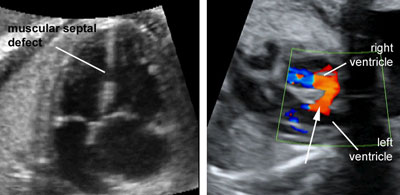

Two-dimensional gray scale imaging of ventricular septal defects

Click the image to magnify it

Legend:Two-dimensional gray scale imaging of ventricular septal defects

Reference(s):Paladini D, Palmieri S, Lamberti A, Teodoro A, Martinelli P, Nappi C. Characterization and natural history of ventricular septal defects in the fetus. Ultrasound Obstet Gynecol 2000;16(2):118–22. PubMed PMID: 11117079.

Color and pulsed Doppler of blood shunting across a muscular ventricular septal defect

Legend:Color and pulsed Doppler of blood shunting across a muscular ventricular septal defect

Axt-Fliedner R, Schwarze A, Smrcek J, Germer U, Krapp M, Gembruch U. Isolated ventricular septal defects detected by color Doppler imaging: evolution during fetal and first year of postnatal life. Ultrasound Obstet Gynecol 2006;27(3):266–73. PubMed PMID: 16485323.

Muscular ventricular septal defect

Legend:Muscular ventricular septal defect